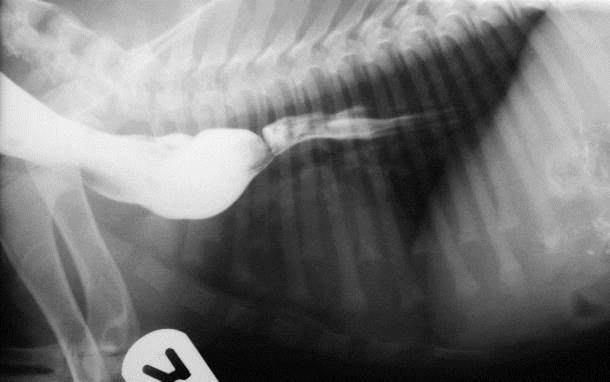

What can be seen here?

Mediastinal mass/fluid

Pleural fluid as lung lobes pushed away from spine

There is a mass here – our mass effect can help – trachea is dorsally elevated and compressed, something solid doing this

Pleural fluid and mediastinal mass